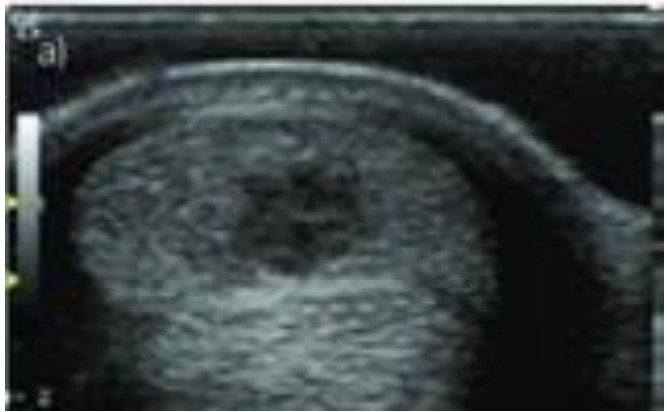

O exame ultrassonográfico dos tendões e ligamentos dos equinos é importante na identificação de lesões e na avaliação da efetividade do tratamento. Observe a imagem abaixo e assinale o enunciado CORRETO que se refere à estrutura anatômica acometida e o diagnóstico.

Fonte: Alzola, R. et al. Ultrasonographic-based predictive factors…. Equine Veterinary Journal. 50. 10.1111/evj.12810.